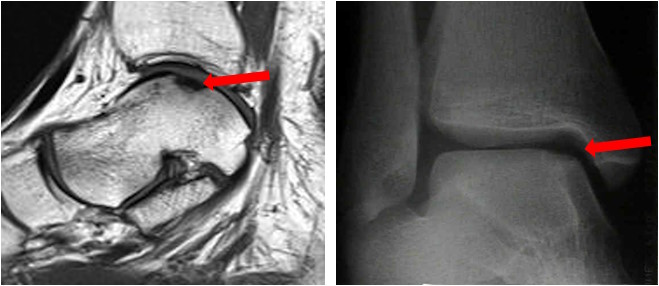

Gesichert wird die Diagnose durch ein bildgebendes Verfahren. Dieses sollte primär aus einer Röntgen-Untersuchung des oberen Sprunggelenks in zwei Ebenen bestehen. Dort lassen sich häufig bereits knöcherne Defekte, insbesondere im Bereich des Sprungbeins darstellen. Zur genauen Beurteilung der Knorpelverletzung dient die Magnetresonanztomographie (MRT). Sie erfasst neben der Knorpelläsion auch Ödeme im Bereich des Knochens und Begleitpathologien wie Sehnenverletzungen oder Bandverletzungen. Die Computertomografie ist hinsichtlich der Darstellung des Knochendefektes dem MRT überlegen und kann in besonderen Fragestellungen ebenfalls indiziert sein.